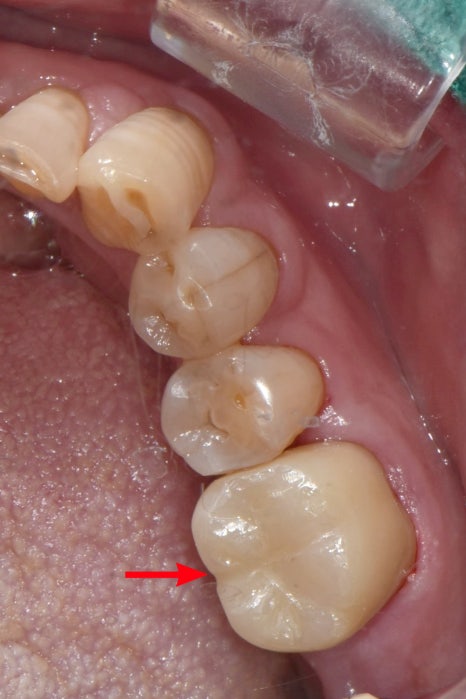

일주일 후,

완성된 지르코니아 보철물을 붙여드렸습니다.

앞 치아와 꽉 맞게 제작 하여,

더이상 음식물이 끼지 않습니다.

지르코니아 크라운 치료 전후 사진입니다.

충치로 인해 지저분하던 치아가 말끔해졌습니다.